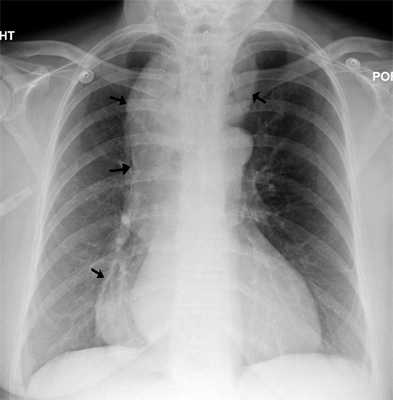

Системная склеродермия представляет собой аутоиммунное заболевание, которое сопровождается васкулитом сосудов мелкого калибра, массивным отложением коллагена, фиброзом гладкой мускулатуры нижних двух третей (гладкомышечной части) пищевода. Симптомы включают проявления тяжелой ГЭРБ и дисфагию, кожа становится натянутой, склерозированной. Необходимо выполнить манометрию и рентгенконтрастное исследование с барием.

При ахалазии пищевода во время манометрии определяется снижение амплитуды сокращений пищевода менее 30 мм рт. ст., повышение давления нижнего пищеводного сфинктера с нарушением его расслабления. При рентгенографии с барием область нижнего пищеводного сфинктера может быть похожа на птичий клюв, иногда определяется уровень «воздух-жидкость», отсутствие перистальтики. При склеродермии также требуется выполнение рентгенографии с барием. Дряблый, расширенный пищевод похож на пищевод при ахалазии, но нижний пищеводный сфинктер проходим.

При манометрии определяется нормальный тонус верхнего пищеводного сфинктера, снижение тонуса нижнего пищеводного сфинктера и отсутствие перистальтики (поскольку поражена только гладкая мускулатура). При ахалазии может проводится последовательное бужирование пищевода; миотомия пищевода, нижнего пищеводного сфинктера и кардии по Heller; инъекции ботулотоксина А в нижний пищеводный сфинктер; прием блокаторов кальциевых каналов для снижения тонуса нижнего пищеводного сфинктера. Поскольку при системной склеродермии функция нижнего пищеводного сфинктера нарушена, ГЭРБ развивается чаще. Лечение состоит в назначении антирефлюксных препаратов, блокаторов кальциевых каналов и системных кортикостероидов.